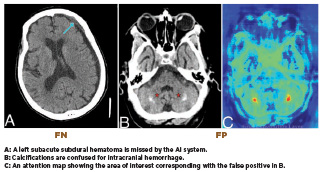

“AI systems are not perfect. They can overcall—mistaking anatomical variations, calcifications, or postoperative changes for pathology like brain hemorrhage— resulting in false positives. They can also under call, particularly missing pulmonary embolism (blockages of blood flow to the lungs caused by blood clots), which are false negatives,” says Matthew Barish, MD, a radiologist, vice chair of informatics for the radiology service line, and chief medical information officer of imaging for Northwell Health in New York City. Because AI-powered software is highly sensitive, errors tend to occur more often in the form of false positives.